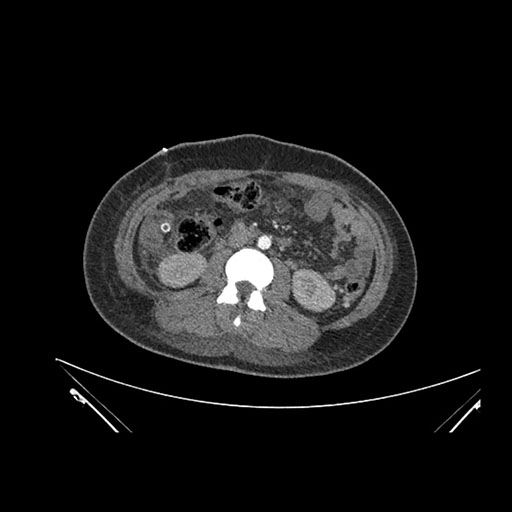

Axial Arterial

Axial Venous